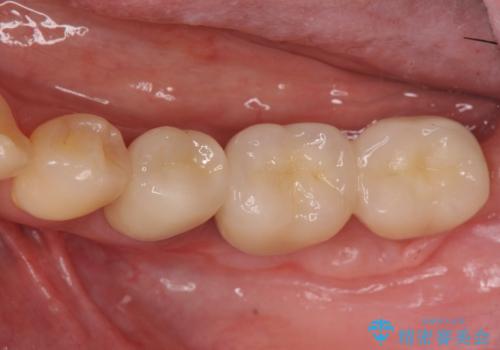

歯ブラシのしやすい環境を整えるインプラント治療

- 歯茎が腫れ、噛めない左下の治療を希望され来院されました。

- 110万円(インプラント×2・チタンカスタムアバットメント×2・ジルコニアクラウン×3・仮歯×3 ・遊離歯肉移植術)費用は治療当時の料金となります

インプラント周囲のお掃除のしやすさを高め、長期的な予後を見込むために、遊離歯肉移植術を行っています。